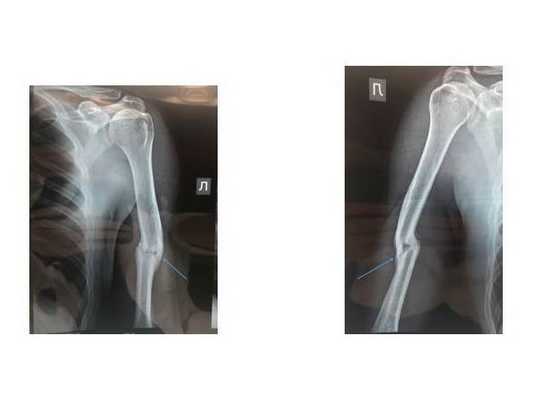

Пациент жаловался на боль и ощущение нестабильности в левом плече, из-за чего рука не работала. При обращении левое плечо было обездвижено гипсом.

Летом 2020 года пациент попал в ДТП и получил закрытый перелом левой плечевой кости. Для лечения обратился в травматологическую клинику Нижнего Новгорода, где ему рекомендовали оперативное лечение — остеосинтез пластиной. Однако пациент отказался от операции и обратился в нашу клинику.

Телосложение спортивное. Рост 180 см, вес 73 кг. Интеллектуальный уровень хороший. Сила кулачного схвата кисти сохранена. Отломки плечевой кости патологически подвижны, при этом появляется хруст и боль в плече.

На рентгенограммах видно перелом средней трети левой плечевой кости с расхождением отломков. Именно из-за расхождения отломков в другой клинике пациенту предложили сделать операцию.

В нашей клинике принято решение лечить перелом без операции — гипсовыми гильзами по методике американского ортопеда Сармиенто. Этот метод широко используется в мире, но в России о нём мало знают и почти не применяют.

Наложена специально выполненная гипсовая гильза (её можно формировать из пластиковых бинтов). Назначена специальная гимнастика. Можно было двигать локтем, выходить на работу (если она не связана с физическим трудом). Через месяц разрешена гантельная гимнастика и лёгкие бытовые нагрузки.

Лечение длилось четыре месяца. Пациент выполнял все рекомендации, в том числе делал упражнения для кисти, плечевого и локтевого сустава. Приходил на контроль один раз в три недели, остальное время находился дома и оставался мобильным, ездил в командировки.

Итогом лечения стало полное восстановление функции руки: объёма движений в плечевом и локтевом суставе и силы кисти. Перелом полностью сросся. Внешних признаков перелома плеча не видно, рука ровная.